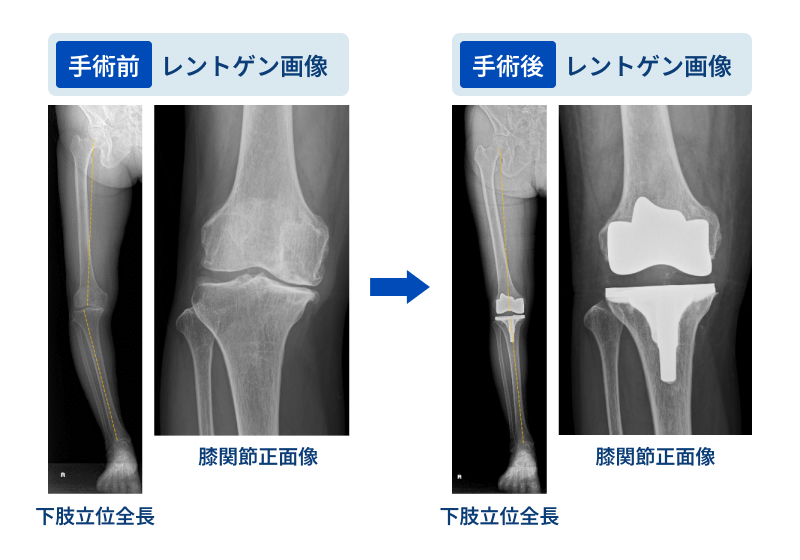

人工膝関節全置換術(TKA)は、中期から末期の変形性膝関節症に対して行う、最も標準的かつ効果的な治療法の一つです。

実際の手術では、傷んでボロボロになった大腿骨(太ももの骨)と脛骨(すねの骨)の関節表面を取り除き、金属やポリエチレンなどでできた人工関節に置き換えます。

手術により頑固な膝の痛みが大幅に改善や関節機能の向上が期待できます。適切なリハビリテーションをする事で歩行能力が回復し、日常生活の質(QOL)が向上します。